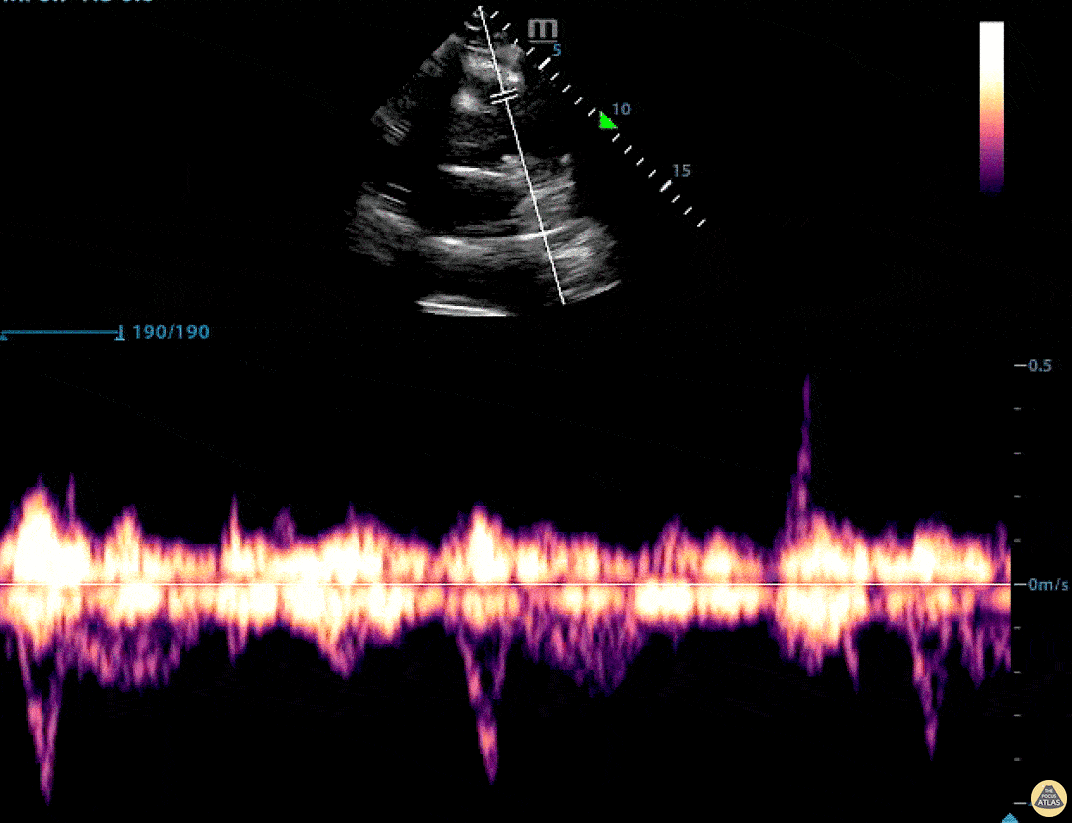

This image shows pulmonary artery mid-systolic notching, a sign of proximal impedance (e.g. PE, pulmonary hypertension), in a 63 yo man without prior pulmonary disease with pulmonary emboli on CTA. From the parasternal short-axis view at the level of the aortic valve (fan anteriorly/superiorly from the mitral valve level), visualize the right ventricular outflow tract, pulmonary valve, and pulmonary artery. Place the pulsed wave Doppler gate about 0.5 cm proximal to the pulmonary valve and generate the waveform by pressing the pulsed wave Doppler button again. Waveforms without impedance (i.e. normal) appear as smooth “domes.” Read more here: PMID 33781986 https://pubmed.ncbi.nlm.nih.gov/33781986/ Robert Adrian, MD. @RobertAdrianMD Emergency Medicine at Rutgers New Jersey Medical School Stephen Alerhand, MD. @SAlerhand Assistant Professor Rutgers New Jersey Medical School